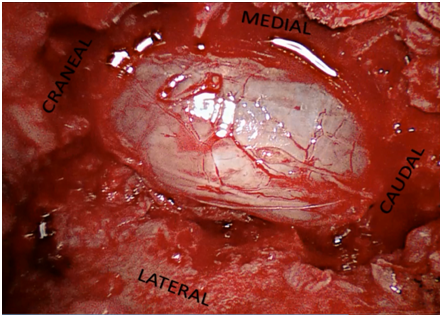

Minimally invasive decompression may be performed using different image intensification methods. Neurosurgeons are familiar with the use of the surgical microscope, which is a good option for this type of procedures. The remarkable contribution of the endoscope as compared to the surgical microscope is that the light of the optic fiber comes from the tip of the working channel, so the instruments may be used without generating any shadows or blind spots. Therefore, very small working channels may be used (16 and 18 mm of diameter), which would be difficult with the surgical microscope for the light is not able to advance through the tube. Also, a 30° angle optic may be used, which is very useful when decompressing the contralateral side (Figures 3,4).

Figure 3 Intraoperative endoscopic photo showing the correct dural release.